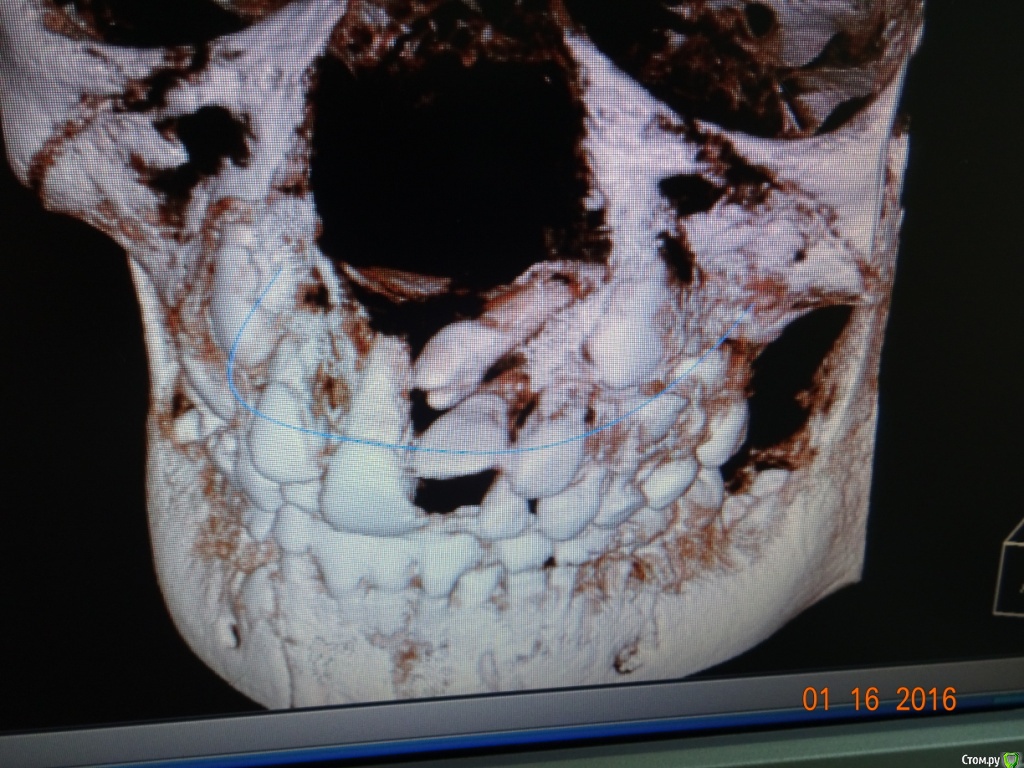

Opdihatop Опубликовано 9 января, 2017 Поделиться Опубликовано 9 января, 2017 Здравствуйте, коллеги! Хотел бы узнать ваше мнение по пациентке. Девочке 7 лет. План лечения в общем мне ясен и понятен. Меня интересует вопрос, когда лучше в данном случае убирать сверхкомплектный премоляр в области 21 зуба, потому что он начал двигать ц.л. вправо. Заранее спасибо! Ссылка на комментарий

Dok22 Опубликовано 11 января, 2017 Поделиться Опубликовано 11 января, 2017 Это не премоляр просто так виден 2-х мерный срез нужно КТ его грамотная интерпретация и хороший хирург.Сверхкомплектный удалять надо он блокирует 21 и 22. Ссылка на комментарий

Dok22 Опубликовано 12 января, 2017 Поделиться Опубликовано 12 января, 2017 С одной стороны вы правы риск повредить 21 22 есть,но если сверхкомплектный 21 сформируется полностью все будет сложнее сейчас при наличии грамотного КТ и хирурга зачаток сверхкомплектного 21 убрать проще.Убирал подобное в 6 и 9 лет в 9 сложнее. Попробую найти КТ выложить. Ссылка на комментарий